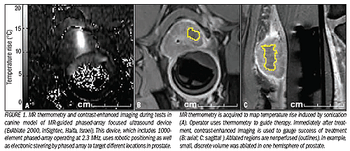

Prostate cancer is a leading cause of cancer death inU.S. men, second only to lung cancer. During2008, an estimated 186,320 new cases of prostatecancer will be diagnosed in the U.S.